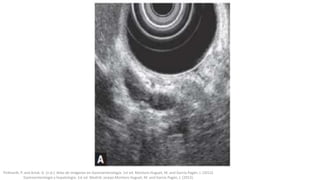

Ecoendoscopia y

colangiorresonancia

La CPRM tiene una gran sensibilidad (95%) y especificidad (89%) respecto

a los cálculos ductales >5 mm, pero puede pasar por alto los cálculos más

pequeños; la ecografía también es muy sensible (95%) y especifica

(100%) y permite la detección de los cálculos ductales pequeños y del

barro biliar.

Su principal inconveniente es que carecen de posibilidades terapéuticas.

Si la ecografía no detecta litiasis, debe hacerse una CPRM o una

ecoendoscopia que confirmen la sospecha diagnóstica.Pickhardt, P. and Arluk, G. (n.d.). Atlas de Imágenes en Gastroenterología. 1st ed. Montoro Huguet, M. and García Pagán, J. (2012).

Gastroenterología y hepatología. 1st ed. Madrid: Jarpyo.Montoro Huguet, M. and García Pagán, J. (2012).